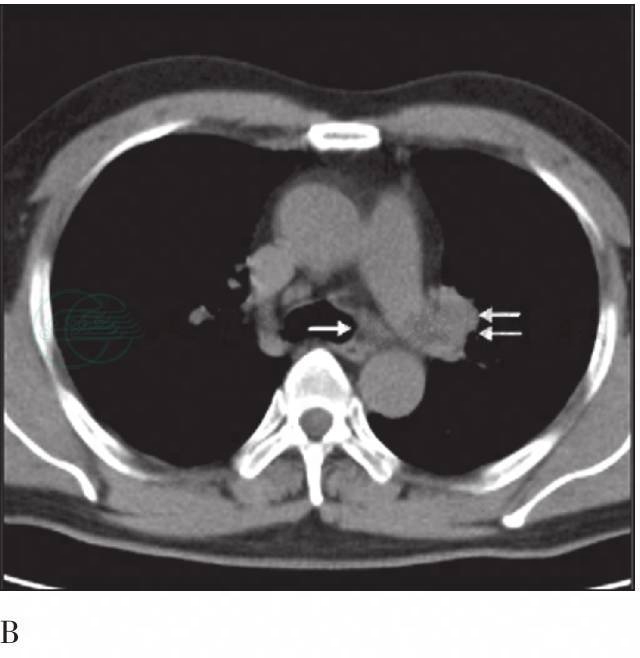

图5 FDG-PET/CT胸部横断面图像

A. PET图像;B. CT图像纵隔窗。纵隔4L区(箭头)及左肺门10L区(双箭头)放射性摄取增高的淋巴结